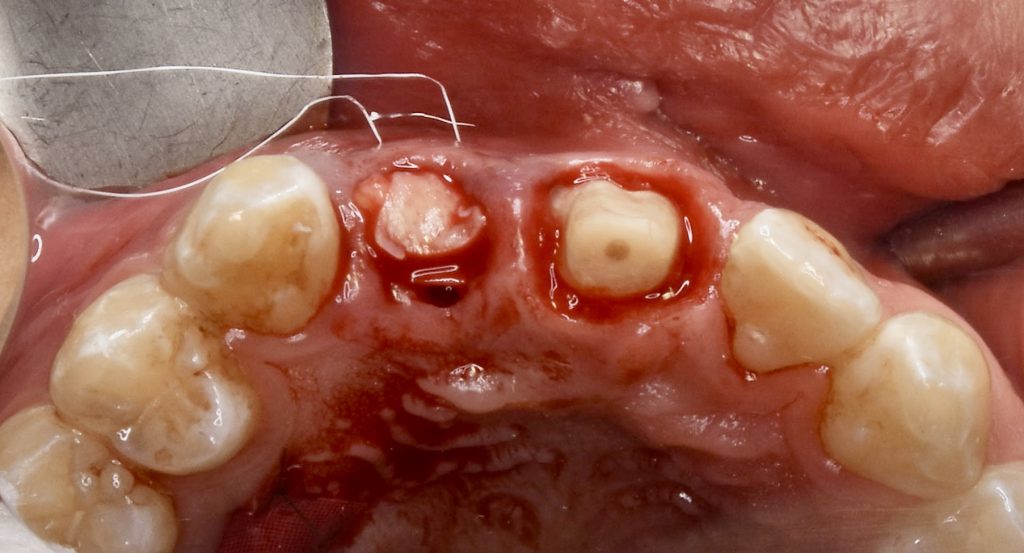

下記の症例は前歯部のインプラント治療において、骨、歯肉の造成をインプラント埋入と同時に行いました。

エビデンスでは抜歯後に唇側骨が吸収していく為、抜歯と同時にインプラント埋入し、非吸収性の骨補填材を充填し、その移植した骨の吸収を最小限に留めておく為に歯肉の厚みが必要です。その歯肉の厚みを確保する為に結合組織を採取しました。